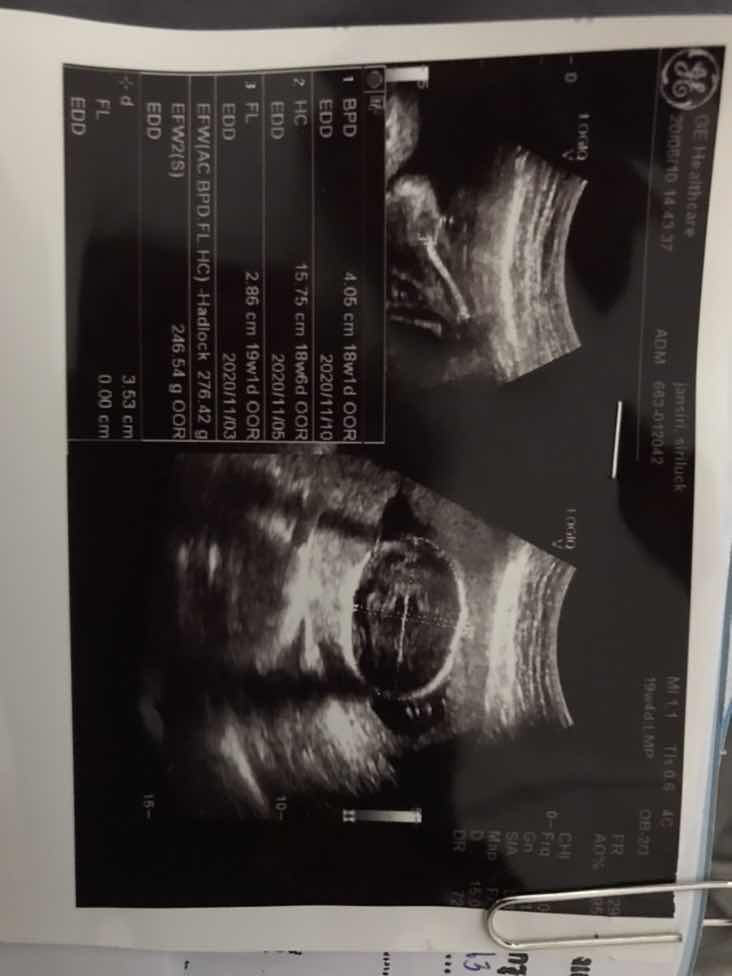

18week กำหนด 8 พ.ย เป็นสาวน้อยจ้า